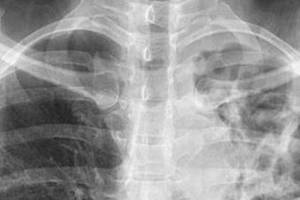

TB screenings set for this month after Kentridge High exposure

Public Health – Seattle King County will test approximately 135 people

About 135 people at Kentridge High to be evaluated for tuberculosis

Steps taken after one person at school diagnosed with active TB; exposure was March to September 2023